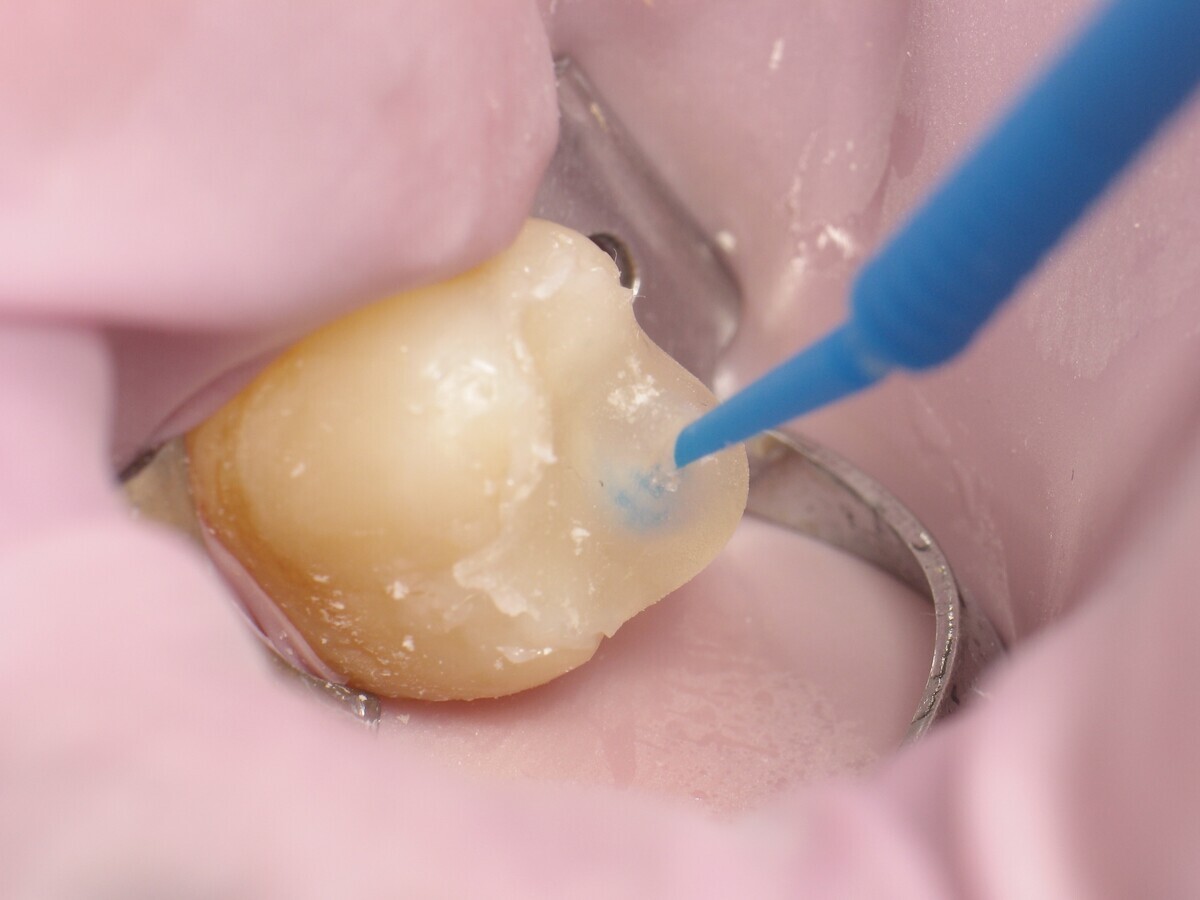

Este artículo describe el tratamiento de una cavidad clase I en un molar utilizando un composite termoviscoso mediante la técnica de la almohadilla (Figura 1). En primer lugar, se registran los detalles anatómicos utilizando una resina transparente, fluida y fotopolimerizable (Clip Flow, VOCO). El diente se aísla con un dique antes de aplicar el composite transparente a la superficie oclusal con un cepillo aplicador y fotopolimerizar durante 10 segundos (Figuras 2-4). La almohadilla oclusal así obtenida (Figura 5) debe almacenarse en alcohol (etanol o isopropanol) para eliminar la capa de inhibición. Luego se limpia la cavidad clase I (Figuras 6 y 7). A continuación se graba el esmalte durante 30 segundos y la dentina durante 15 segundos (Conditioner 36, Dentsply Sirona) y luego se enjuaga bien (Figuras 8 a 10). Debido al bajo espesor de la dentina remanente, también se aplica protección pulpar (Telio Desensitizer, Ivoclar Vivadent) (Figura 11). Luego se frota el adhesivo sobre las superficies dentales durante 20 segundos (Futurabond DC, VOCO), luego se seca bajo una pulverización de aire sin aceite graso durante 5 segundos y luego se fotopolimeriza durante 10 segundos (Figuras 12, 13). Para una humectación óptima, el fondo de la cavidad se cubre con un compuesto fluido de baja viscosidad (GrandioSO Light Flow, A3.5, VOCO) y se fotopolimeriza durante 20 segundos (Figuras 14, 15). Utilizando el Dispensador VisCalor, un dispensador portátil que permite el calentamiento y la aplicación simultánea de resinas, la cavidad se llena luego con un composite termoviscoso bulk (VisCalor Bulk, A2, VOCO).

Figura 12. Cavidad después de la aplicación de Futurabond DC.

Figura 13. Fotopolimerización del adhesivo.